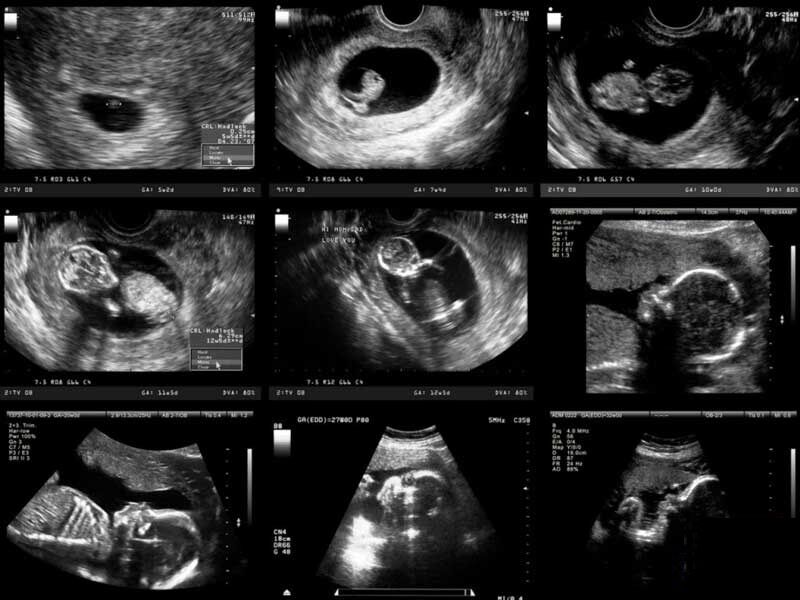

دکتر فیروزه احمدی- متخصص سونوگرافی و رادیولوژی در ارتباط با سونوگرافیهای مهم و روتین که در بارداری استفاده میشود توضیح میدهد: «اولین سونوگرافی که معمولا درخواست میشود در هفته ۶ تا ۷ بارداری است؛ برای مشخص کردن محل ساک بارداری، تعداد ساک و جنینها و همچنین دیدن ضربان قلب. سونوگرافیهای روتین بعدی با این سونوگرافی اول از نظر رشد جنین مقایسه میشود».

این متخصص سونوگرافی ادامه می دهد : «سونوگرافی بعدی که اصطلاحا به آن غربالگری اول گفته میشود، معمولاً بین هفته ۱۱ تا ۱۳ انجام میشود. طی این غربالگری ضخامت پشت گردن جنین را اندازه گیری میکنند و ناهنجاریهای اساسی و مهم که ممکن است در این سن خود را نشان بدهند، بررسی میشود».

عضو هیئت علمی پژوهشگاه رویان ادامه میدهد: «به سونوگرافی بعدی که انجام میشود غربالگری دوم گفته میشود که اصولاً بین هفته ۱۸ تا ۲۲ است. این سونوگرافی غربالگری در کشور ما قبل از هفته ۲۰ انجام می شود که بازدر آن رشد جنین را بررسی و مقایسه میکنند. در این سن ناهنجاریهایی که ممکن است جنین در ظاهر داشته باشد و همچنین علائمی که ممکن است نشان دهنده بعضی از سندرومهای مادرزادی باشد قابل بررسی است. ولی مهمترین علل انجام این سونوگرافی عبارتند از: بررسی رشد جنین، میزان مایعی که دور جنین است، بررسی ضربان قلب جنین و ناهنجاریهایی که ممکن است در ظاهر جنین مشخص باشد. سونوگرافی بعدی اگر لازم باشد معمولا بین هفته ۲۸ تا ۳۲ است که مجددا بررسی وزنگیری، میزان مایع و رشد جنین است. موقعیت جنین و جفت برای این که پزشک در ارتباط با زمان زایمان تصمیم بگیرد مشخص میشود و اگر لازم باشد داروهای لازم و متناسب با رشد جنین به مادر داده میشود».